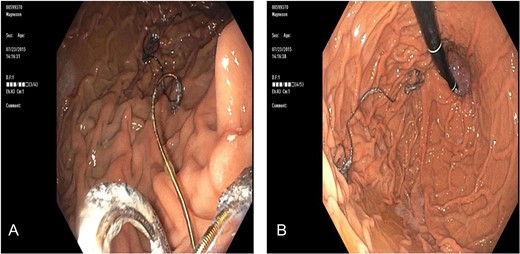

A 65 -year-old woman with a known history of multiple splenic and hepatic aneurysms was admitted to our hospital in October 2012 with acute abdomen. Abdominal computed tomography angiography showed rupture of splenic aneurysm with active extravasation of contrast and associated large left upper quadrant hematoma with small hemoperitoneum (Fig. 1). Visceral angiogram confirmed the presence of three fusiform aneurysms involving midsplenic artery (Fig. 2). The distal most aneurysm demonstrated large extravasation (Fig. 3). Coil embolization of the proximal and midsplenic artery aneurysm was performed using multiple Nester coils (Cook Medical, USA) with cessation of antegrade flow (Fig. 4). Attempt to access distal portion of the splenic artery was unsuccessful. She recovered well and was discharged 4 days later. In December 2016, she was admitted with dyspepsia and severe iron deficiency anemia requiring blood transfusion. A colonoscopy and upper endoscopy were performed which showed the presence of metallic coils in the stomach (Fig. 5). The patient subsequently underwent a combined upper endoscopy and laparoscopy. Three 5 mm ports were used to expose the lesser sac in event of hemorrhage during extraction of the coil endoscopically. An atraumatic bowel clamp was placed distal to the Treitz ligament to prevent insufflation of the small bowel. Upper endoscopy was performed using CO2 insufflation and the Nester coils were retrieved using rat tooth forceps (Fig. 6). There was no bleeding in the lesser sac after removal of the coils. A leak test was performed to rule out gastric perforation. She had an uneventful recovery and was discharged the next day.

(A) Endoscopy showed wire strands in the fundus of the stomach and (B) occluding the pylorus.